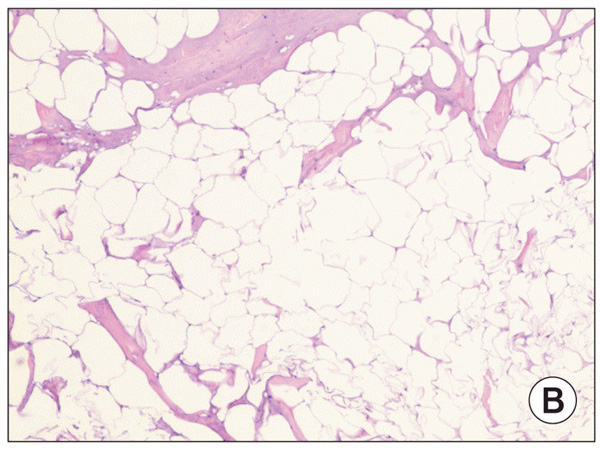

Гистопатологические данные в подкожно-жировом слое

Гистопатологические данные в подкожно-жировом слое свиней после радиочастотной обработки (окрашивание Н&Е, х20)

сморщенные адипоциты

Многие сморщенные адипоциты видны в жировых слоях с отсутствующей воспалительной клеточной инфильтрацией (х40)